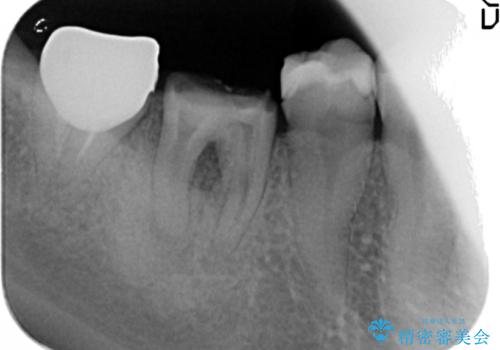

銀歯の下に大きな虫歯の再発

- 銀歯が脱離し、再装着を求めて来院されました。

脱離した歯を精査したところ、大きな虫歯の再発・穿孔箇所が複数認められ長期的な予後を見込むことが難しかったため抜去が妥当であると診断しました。